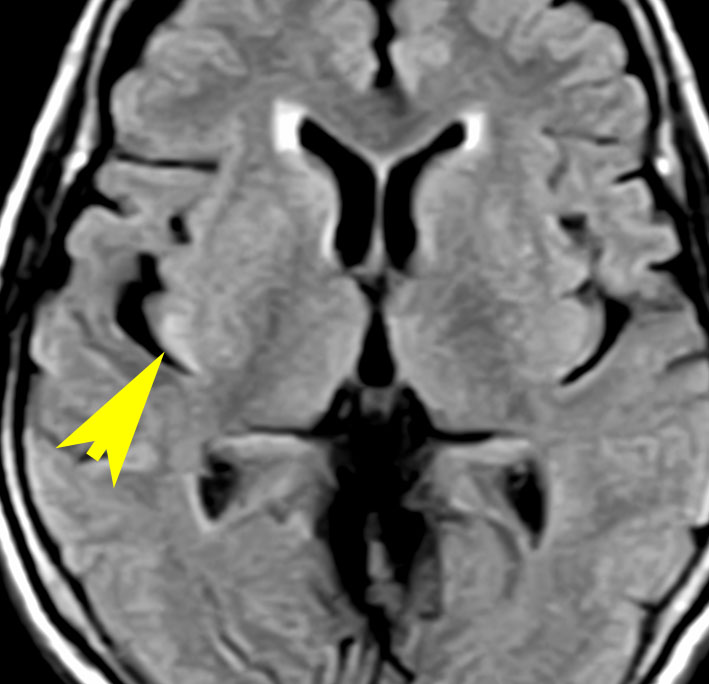

T2-FLAIR mismatch sign (T2とフレアの信号が違うこと)

protoplasmic astrocytomaに特徴的なMRI所見です。T2強調画像(左側)では白く(強い均一な高信号)見えます。でもフレア画像(右側)では白く縁取ったように見えます。びまん性星細胞腫の大きな特徴とされます。内部がとても柔らかいドロドロした腫瘍のこともあります。

mucoid degenerationを含むprotoplasmic astrocytomaの像です。グレード2の典型的病理像です。